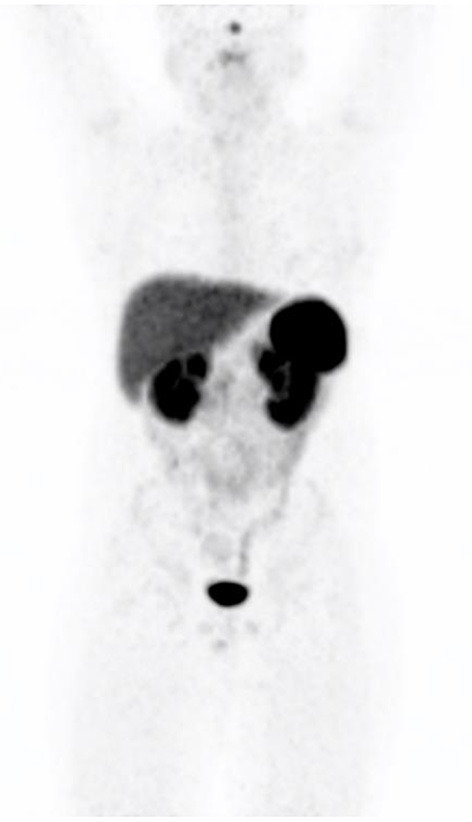

三十多年来,Indium 111 DTPA Octreotide(Octreoscan)一直是核医学生长抑素受体(SSTR)成像的支柱。PET/CT的出现带来了生长抑素的新类似物,由于其标记用于正电子成像的镓68,因此具有更高的亲和力和改进的分辨率。最常用的类似物包括DOTATATE、DOTATOC和DOTANOC。然而,镓68–1,4,7,10-四氮杂环十二烷-1,4,7,10-四乙酸(DOTA)-奥曲酸(DOTATE)可能是最常见的非FDG(氟-2-脱氧葡萄糖)PET示踪剂,与PSMA(前列腺特异性膜抗原)并列。与F18标记的FDG相比,由于Ga68发生器的可用性,它不需要接近回旋加速器。DOTATATE是一种生长抑素类似物,可以对细胞表面的生长抑素受体进行全身成像。68Ga-DOTA化合物为高分化(1级和低2级)神经内分泌肿瘤(NETs)提供了成像标准,并用于NETs患者的分期、表征和再分期。68Ga-DOTATE与18F-FDG具有互补作用,其中肿瘤可能表现出不同程度的分化。此外,它还可作为治疗的前奏,用于选择使用治疗方法进行肽受体放射性核素治疗的患者。对放射性示踪剂的正常生物分布有充分的了解,对于最佳的患者结果和避免潜在的假阳性(如炎症、正常的胰腺钩突摄取和成骨细胞活性)至关重要。在这篇综述中,我们将在图像的支持下描述68Ga-DOTATE的正常外观和潜在的陷阱,以帮助改进对这一关键创新工具的解释,从而管理表达SSTR的肿瘤个体。

Indium 111 DTPA Octreotide (Octreoscan) has been the pillar of Somatostatin receptor (SSTRs) imaging in nuclear medicine for over three decades. The advent of PET/CT brought new analogs of somatostatin that have higher affinity and improved resolution due to their labeling to Gallium 68 for positron imaging. The most used analogs include DOTATATE, DOTATOC and DOTANOC. However, Gallium 68-1,4,7,10-tetraazacyclododecane-1,4,7,10-tetraacetic acid (DOTA)-octreotate (DOTATATE) is probably the most common non-FDG (fluoro-2-deoxy glucose) PET tracer alongside PSMA (prostate specific membrane antigen). In contrast to F18-labeled FDG, it does not require proximity to a cyclotron due to the availability of the Ga68 generator. DOTATATE is a somatostatin analog which allows whole body imaging of somatostatin receptors on cell surfaces. 68Ga-DOTA compounds provide the imaging standard for well-differentiated (Grade 1 and low grade 2) neuro-endocrine tumors (NETs) and is utilized in the staging and characterization and restaging of patients with NETs. 68Ga DOTATATE has a complementary role with 18F-FDG where tumors may exhibit varying degrees of differentiation. It furthermore has application as a prelude to therapy in selecting patients for peptide receptor radionuclide therapy using a theranostic approach. A sound knowledge of the normal biodistribution of the radiotracer is imperative for optimal patient outcome and to avoid potential false positives such as inflammation, normal pancreatic uncinate process uptake and osteoblastic activity. In this review, we will describe the normal appearances of the 68Ga DOTATATE and the potential pitfalls with the support of images to aid in improving interpretation of this crucial innovative tool in the management of individuals with tumors expressing SSTRs.